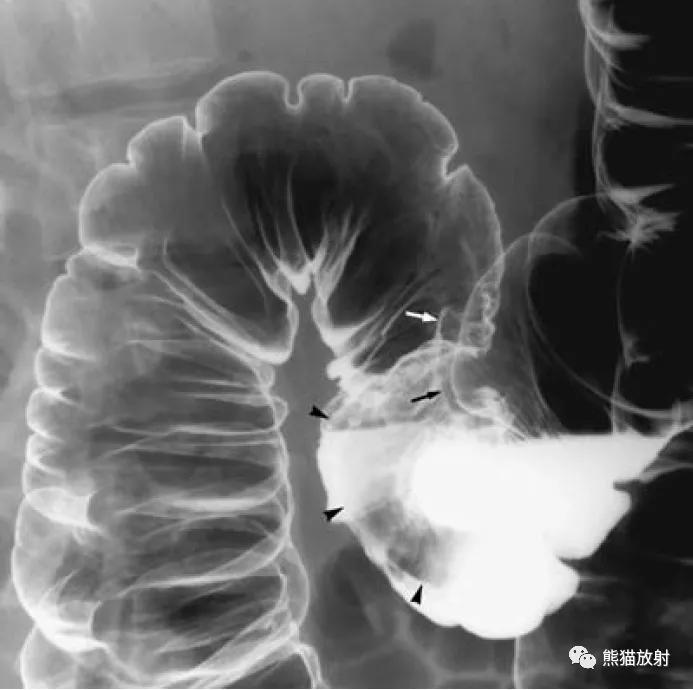

盲肠扭转。X线摄片显示中腹部肠管明显扩张(箭头)。钡餐检查示升结肠扭曲部位可见特征性的鸟嘴征(箭头)。

结-结肠肠套叠,由盲肠癌所致。钡灌肠显示横结肠中的肠套叠(箭头),在进一步的压力下,肠套叠移位至升结肠。

回-结肠套叠。CT定位像示7岁患儿的肠套叠(箭头)。Burkitt淋巴瘤所致。右图:10个月大的婴儿,疼痛和右上腹肿块。X线平片示横结肠(箭头)区域有软组织肿块。钡灌肠证实为肠套叠。